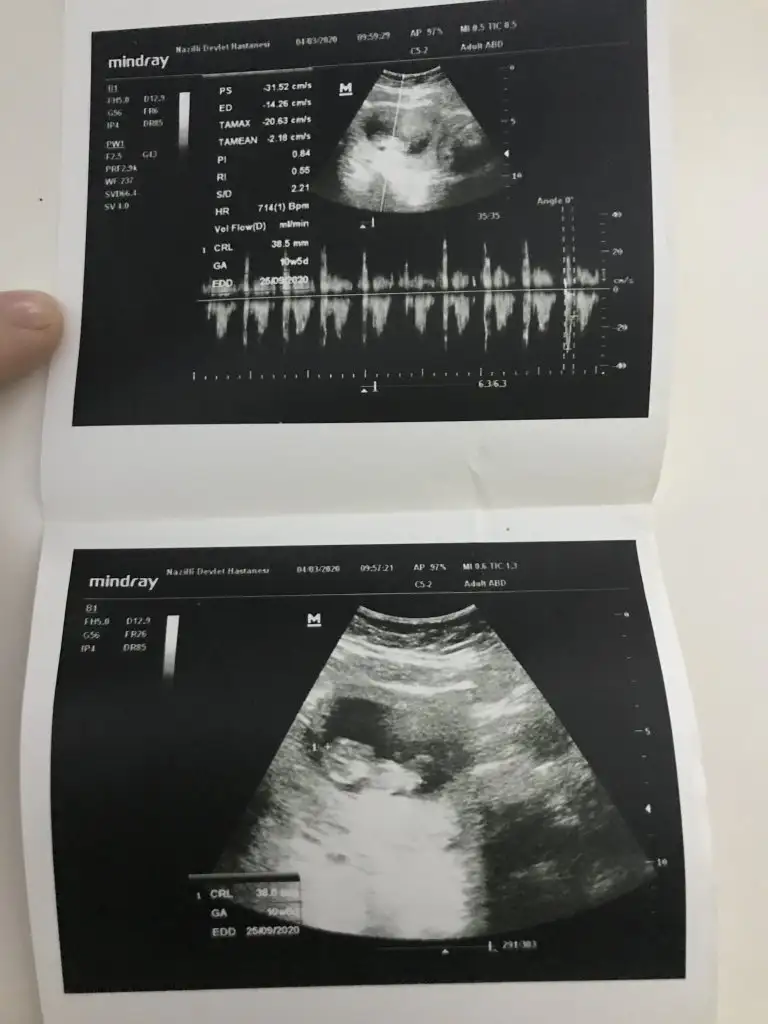

11 yada 12 hafta usg varsa bakabilirmiyim

Maalesef yok 10 haftalık ve kesenin fotoğrafı var 7 haftalık onları bi atiyim size11 yada 12 hafta usg varsa bakabilirmiyim

Bunlara göre kız sanki nette değil usg ama kese kız yönündeMaalesef yok 10 haftalık ve kesenin fotoğrafı var 7 haftalık onları bi atiyim size